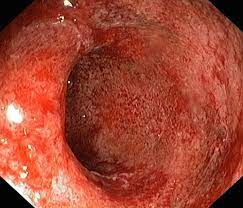

- Rektumda ülserler

- Rektoskopiile biyopsi

- Sigmoidoskopiile biyopsi

- Endosonografi ile biyopsi